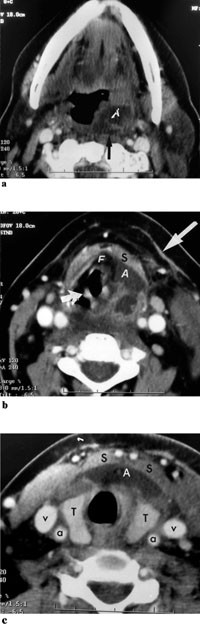

CT collum viste utbredt abscedering på halsen, mest på venstre side. I tonsillnivå bar dette preg av peritonsillær abscess med ødem i retrofaryngealrommet. Ødemet bredte seg langs bakveggen i oropharynx/hypopharynx med engasjement av submukøst rom på innsiden av tungebeinet. Abscederingen strakte seg langs fremkanten av thyreoidea og inn mellom muskellagene foran på halsen (fig 3 a, b, c).

I vårt tilfelle så det ut til at kirurgisk debridement hadde stor betydning for den kliniske tilstanden (fig 1, fig 2). Det skal i denne sammenheng nevnes at trombosering av v. jugularis interna ofte blir beskrevet som en del av Lemierres syndrom. I Lemierres artikkel blir det nevnt at man ved å ligere v. jugularis interna i noen tilfeller kunne forhindre spredning av infeksjonen fra det peritonsillære rommet. Vi avstod fra dette, da det i vårt tilfelle ikke var radiologiske tegn til trombosering av venen (fig 3).